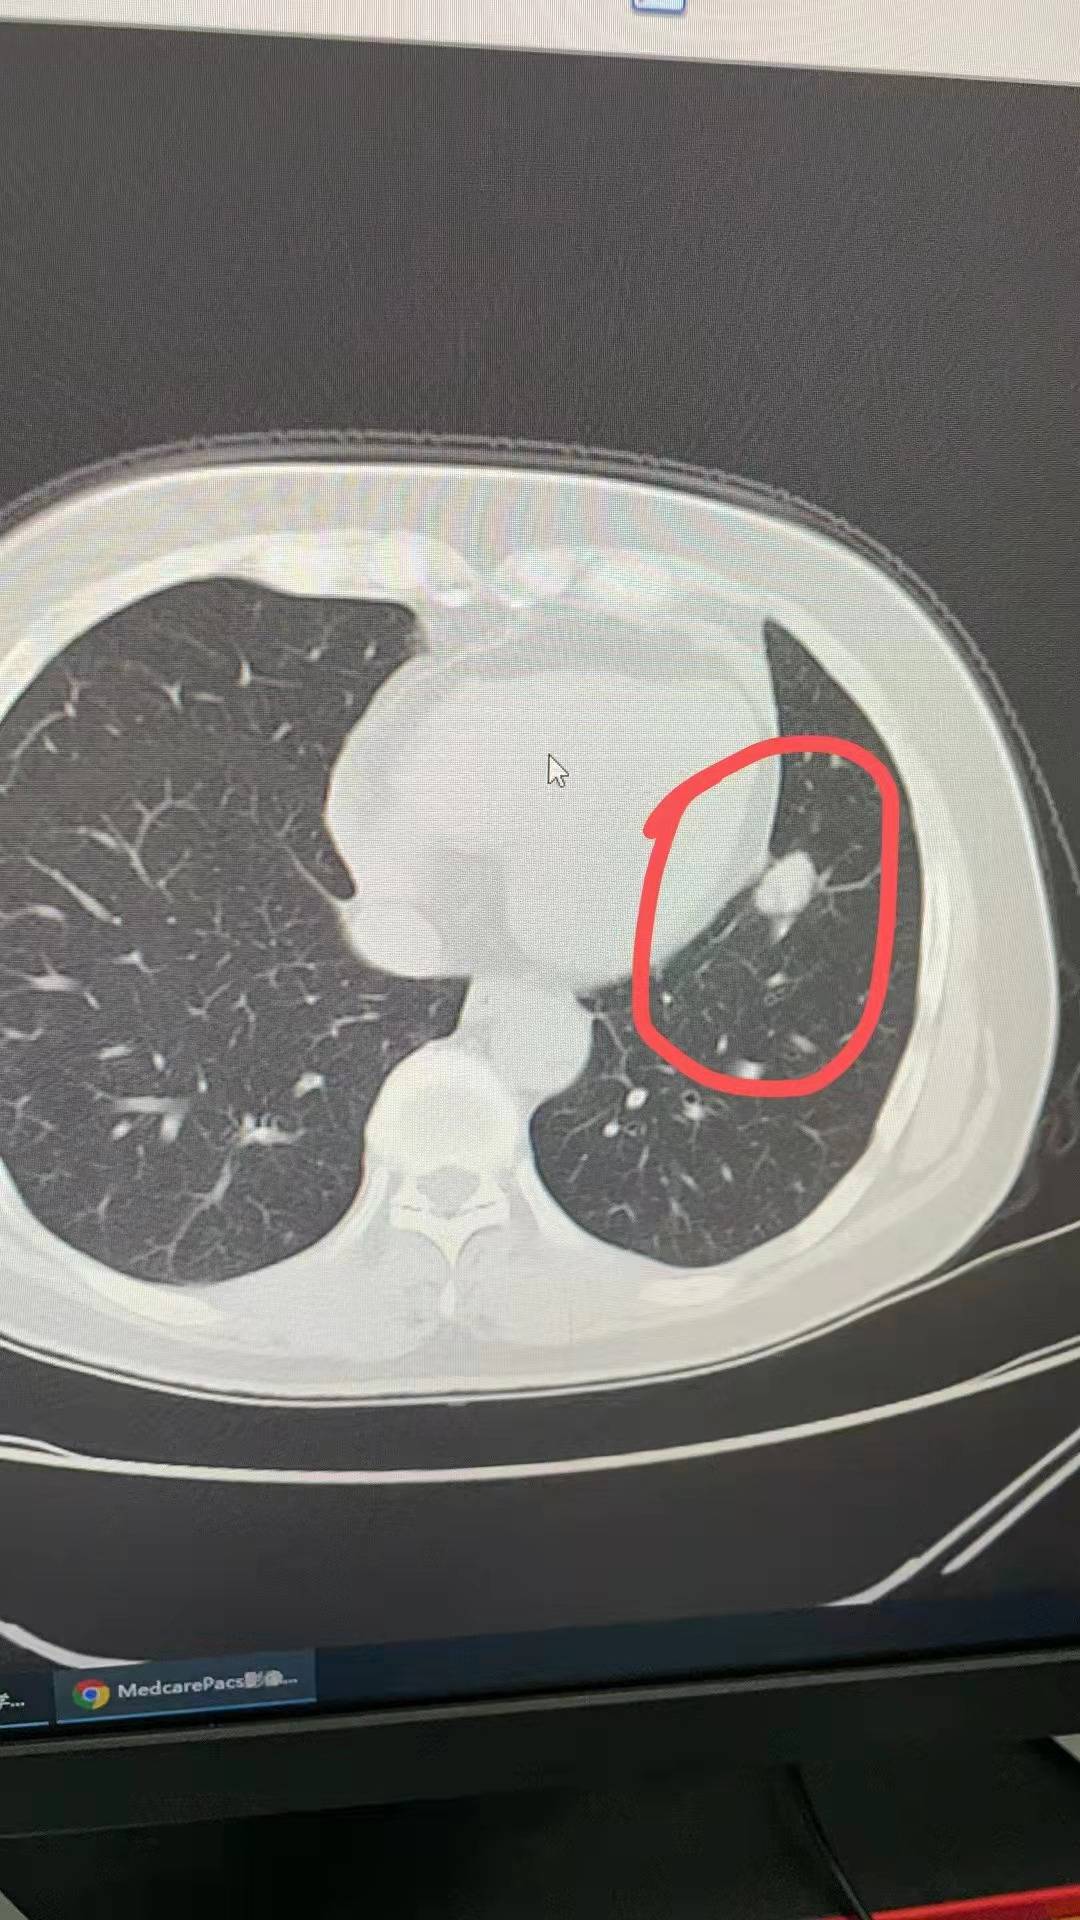

增强CT:肺窗截面8.7mm*5.2mm,多发磨玻璃结节4mm。初诊增强CT:肺窗截面18mm*13mm,多发磨玻璃结节4mm,左肺门淋巴转移23*16mm,纵膈淋巴结转移短径12mm,骨骼转移需观察,明显好转有效治疗[胜利]